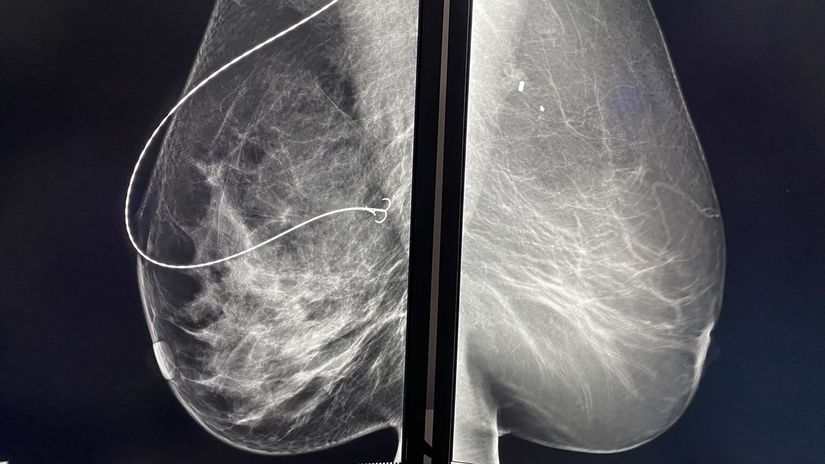

Drôtik (naľavo) verzus magnetické zrno pod rtg. Foto: NOÚ

rakovina prsníka, prsník, karcinóm prsníka, magnetické zrno, drôtik Drôtik (naľavo) verzus magnetické zrno pod rtg.